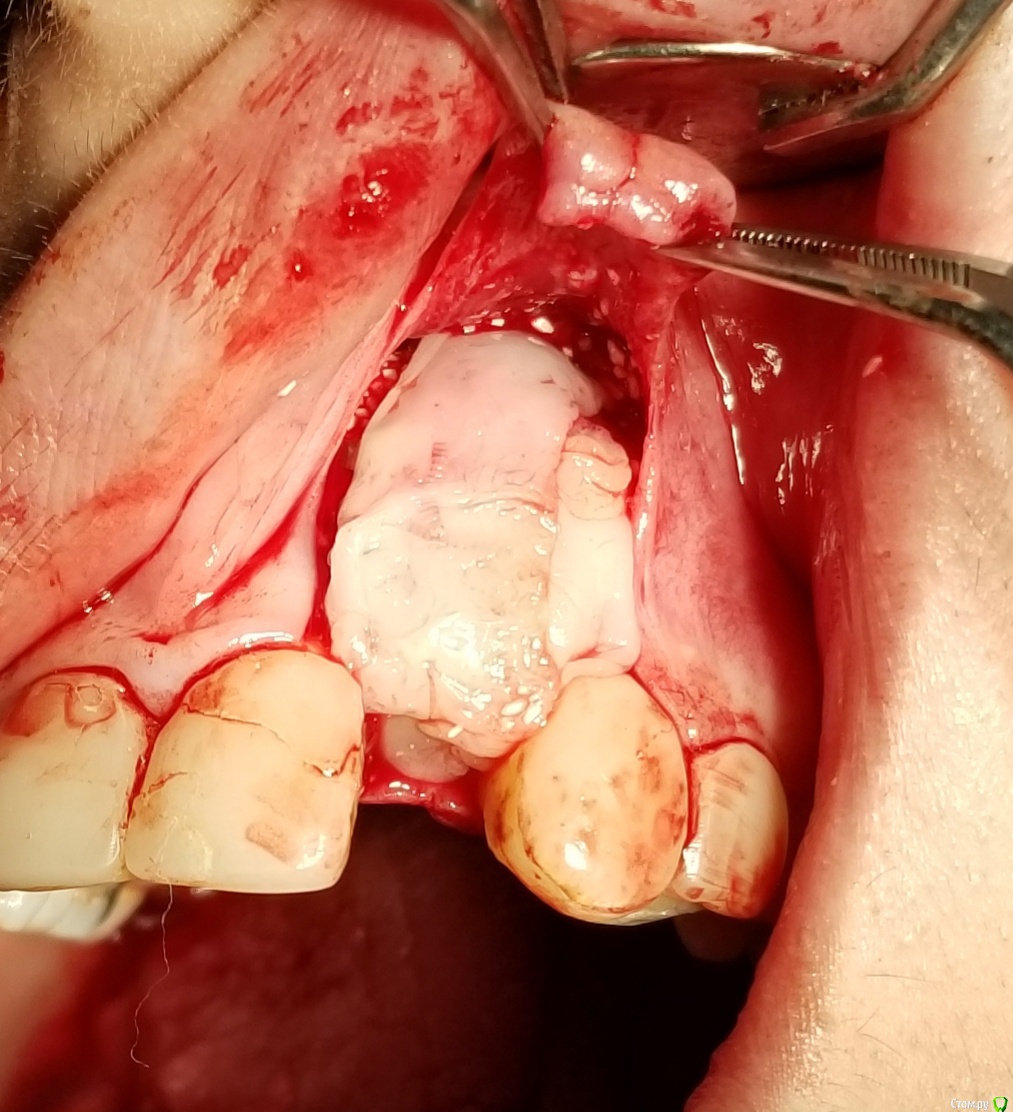

Kostoprav Опубликовано 18 сентября, 2018 Поделиться Опубликовано 18 сентября, 2018 Апатос+ ПРФ+ инъекционный ПРФ+ титановая мембрана.кт через 4,5 мес.Честно говоря кости ожидал побольше, так как паковал с гиперобобьемом. Ссылка на комментарий

stommm Опубликовано 20 сентября, 2018 Поделиться Опубликовано 20 сентября, 2018 Имхо для такого дефекта лучше сетку подлиннее (у нео есть такие) что бы апекально фиксировать в кости, а не так что апекальный край сетки лежит над дефектом. И Имплант по фото недогазлублен. Либо профиль неудачный будет, либо коронка короткая. При бОльшем заглублении имхо получилось бы лучше Ссылка на комментарий

L.E.S.I.K. Опубликовано 20 сентября, 2018 Поделиться Опубликовано 20 сентября, 2018 В инструкциях производителя этот тип мембран не предназначен для апекальной фиксации, есть мембраны с проререзями под винты но у нас таких не продают.Такие мембраны я просто припиниваю. Или можно закрутить винтом, предварительно просверлив. Ссылка на комментарий

АнтонТЛТ Опубликовано 20 сентября, 2018 Поделиться Опубликовано 20 сентября, 2018 имплант с полированой шейкой, эго не желательно сильно погружать под кость.В инструкциях производителя этот тип мембран не предназначен для апекальной фиксации, есть мембраны с проререзями под винты но у нас таких не продают.Только шейка не полированная, а фрезерованная. Мембраны с прорезями это более новый вид. Мембраны без прорезей можно пробивать пином или пин/винт крепить между ножек. В вашем случае, если не прибивать, то надо было мембрану лучше загнуть или взять больший размер, чтобы мембрана опиралась на кость апикально. 2 Ссылка на комментарий